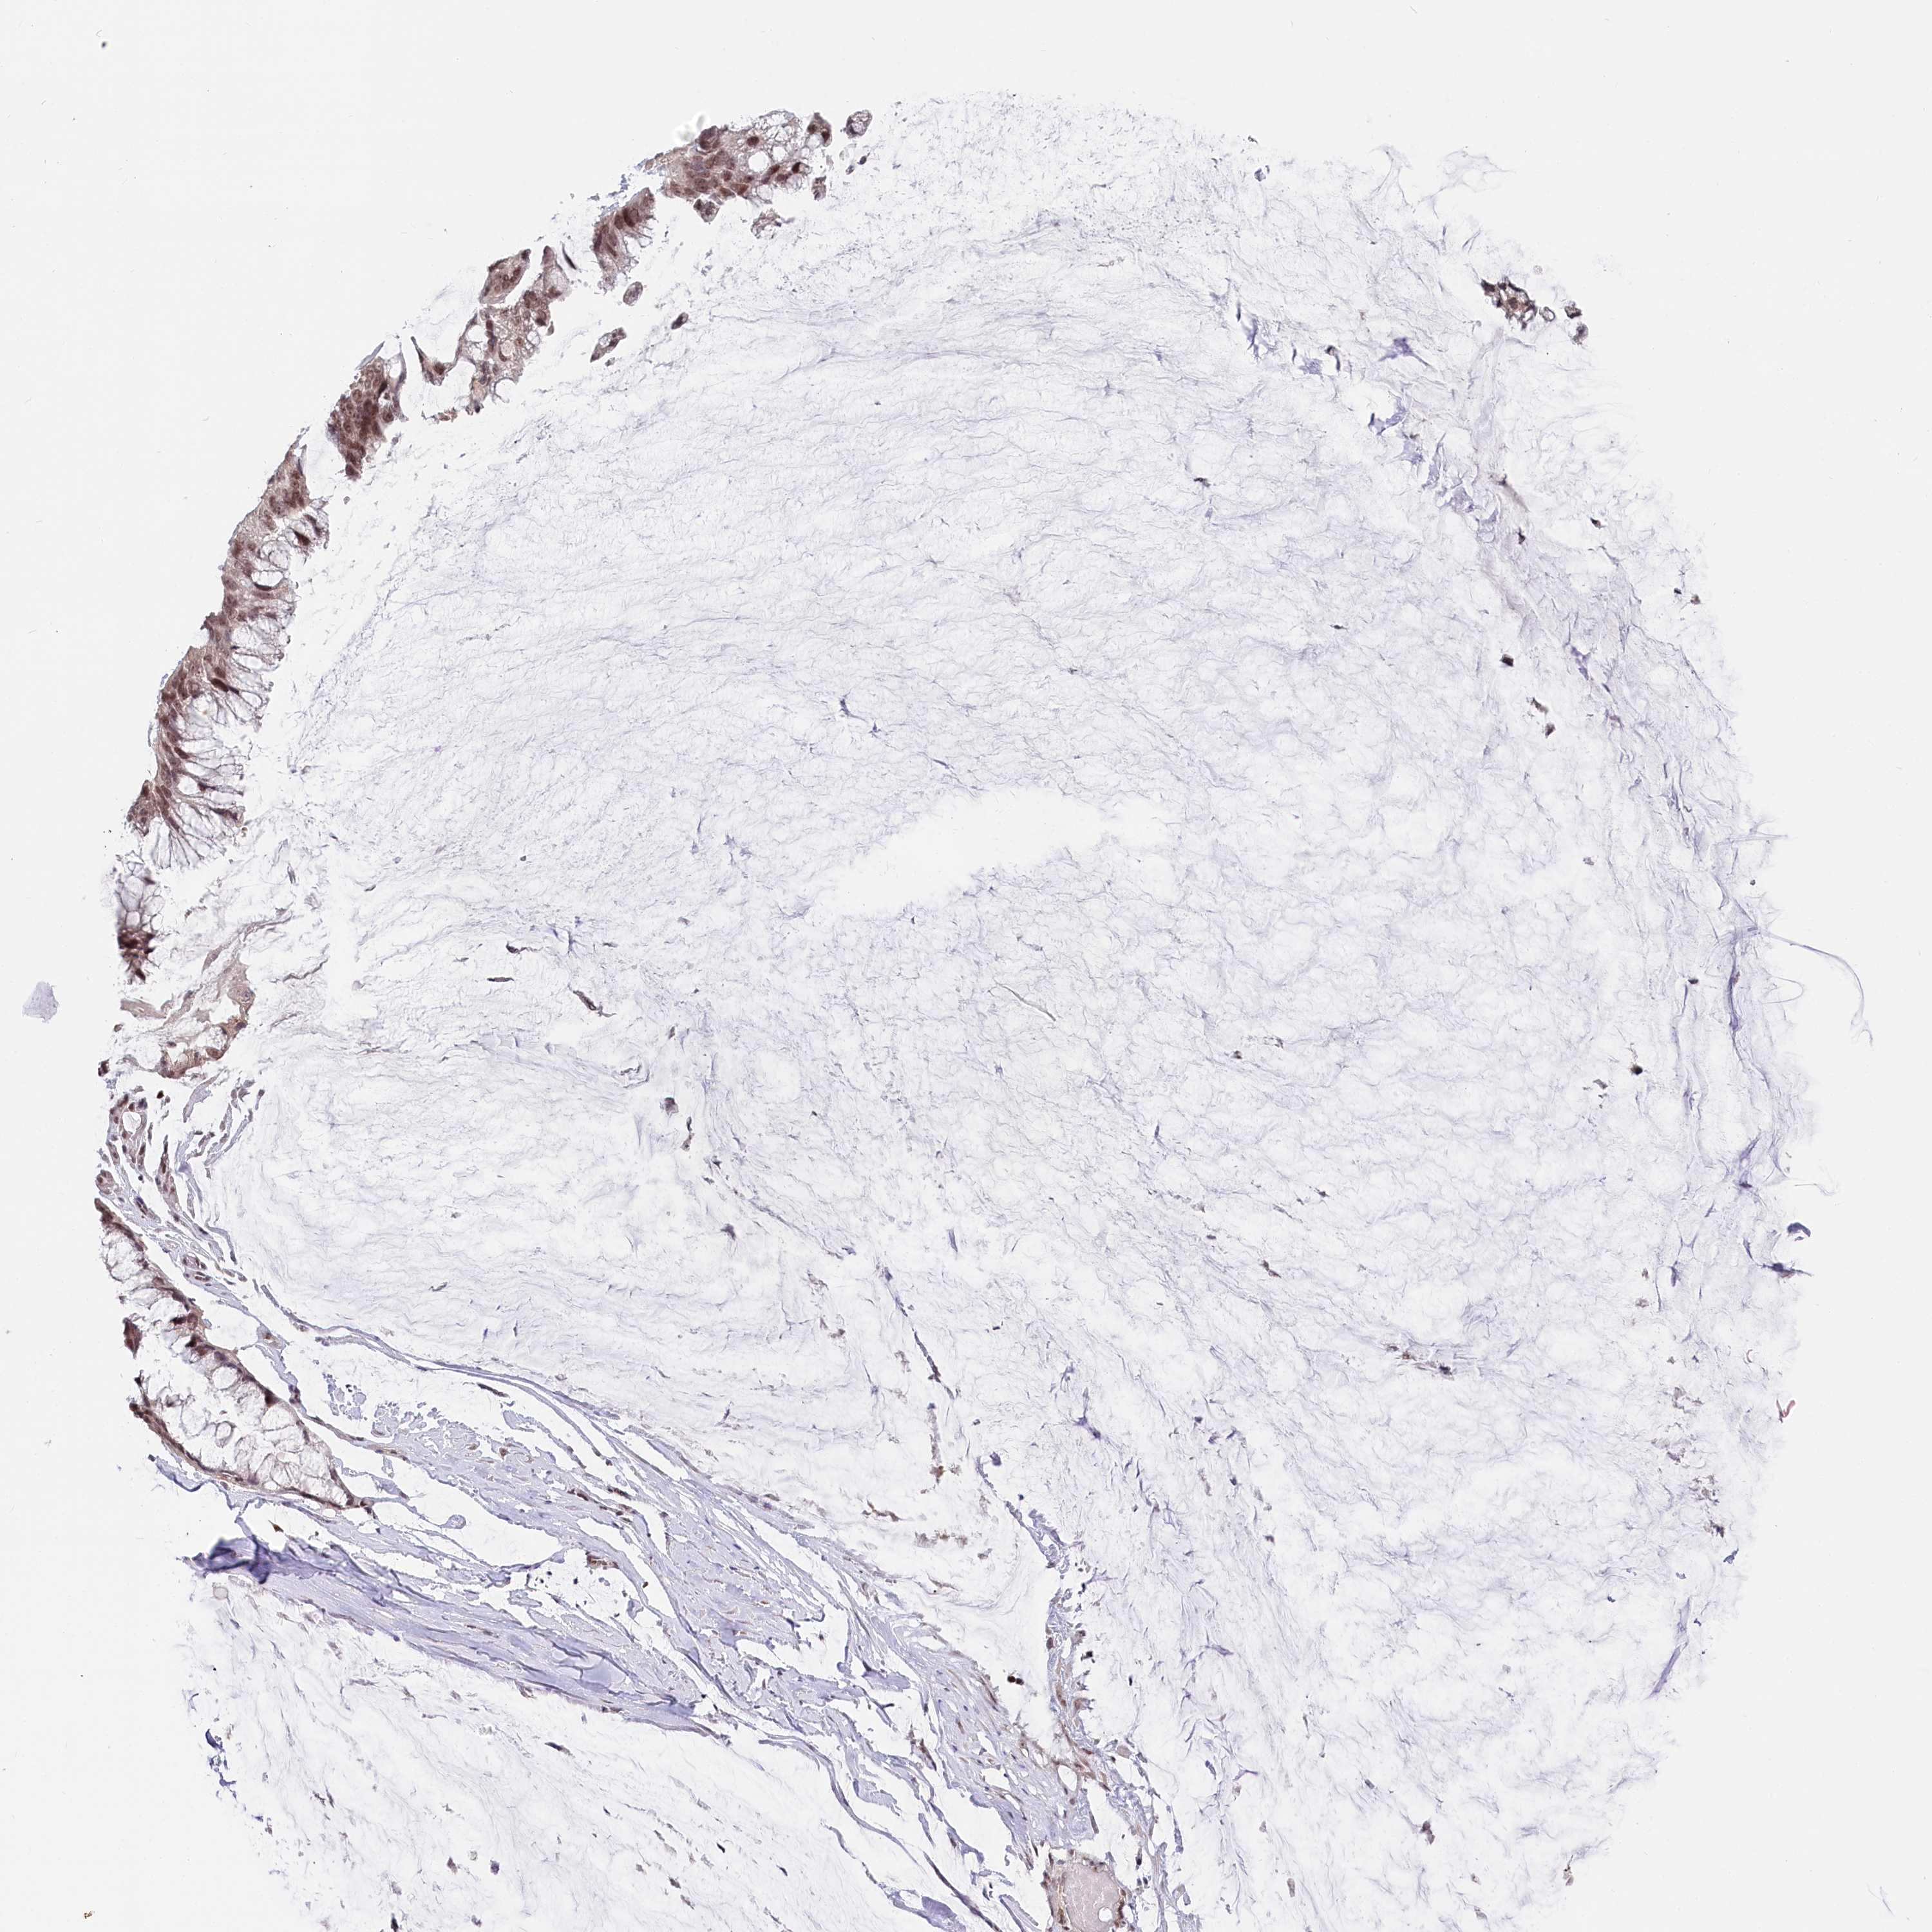

OVARIAN CANCER - Protein expressioni

A mouse-over function shows sample information and annotation data. Click on an image to view it in a full screen mode. Samples can be filtered based on level of antibody staining by selecting one or several of the following categories: high, medium, low and not detected. The assay and annotation is described here.

Note that samples used for immunohistochemistry by the Human Protein Atlas do not correspond to samples in the TCGA dataset.

Antibody stainingi

Antibody staining in the annotated cell types in the current human tissue is reported as not detected, low, medium, or high, based on conventional immunohistochemistry profiling in selected tissues. This score is based on the combination of the staining intensity and fraction of stained cells.

Each image is clickable and will lead to virtual microscopy that enables deeper exploration of all samples and also displays staining intensity scores, fraction scores and subcellular localization as well as patient and tissue information for each sample.

Antibody HPA035568

Antibody HPA037017

Cystadenocarcinoma, serous, NOS

Carcinoma, endometroid

Cystadenocarcinoma, mucinous, NOS

Carcinoma, NOS